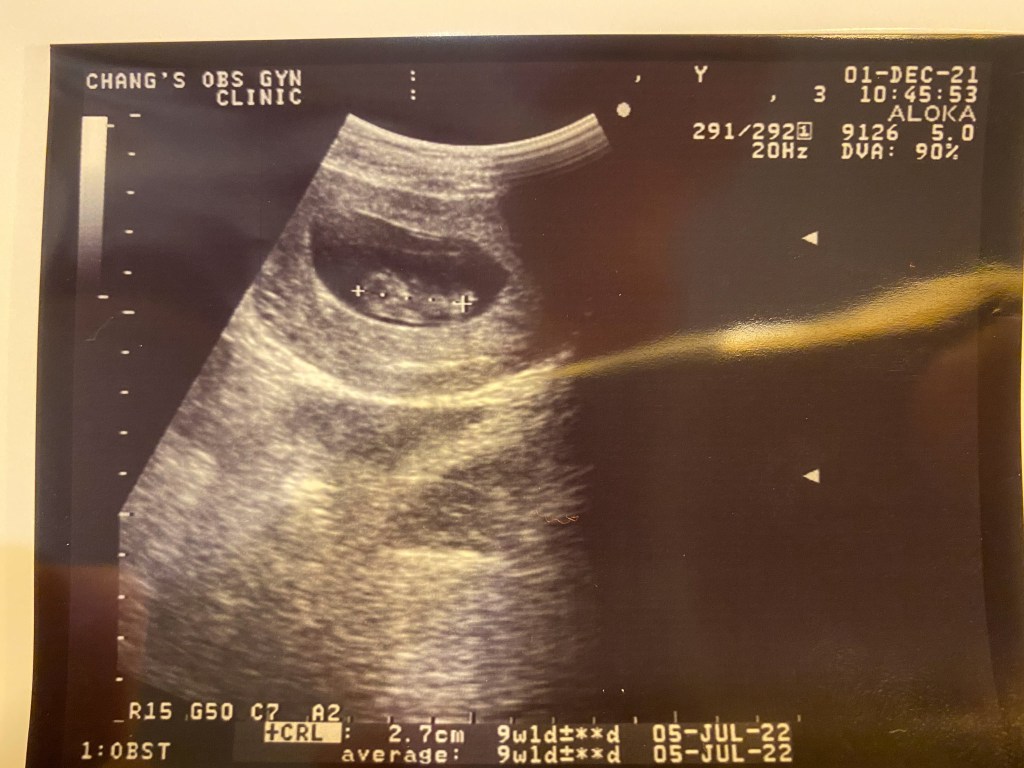

For those who didn’t get it – we are pregnant! (I say we but we know it’s just Amber lol..) She is at 9 weeks so it is still early and is feeling the effects of pregnancy in a strong way. With Hezekiah, Amber was also extremely sick for almost the entire pregnancy and we are just hoping that it doesn’t look the same way this time. As of now, since we have a toddler this time, I have been hard at work trying to stay active in ministry while taking care of Amber and Hezekiah and it is a bit more work than I expected but God is giving me grace as I pray for energy to manage each day. Prayers for these things would be wonderful!